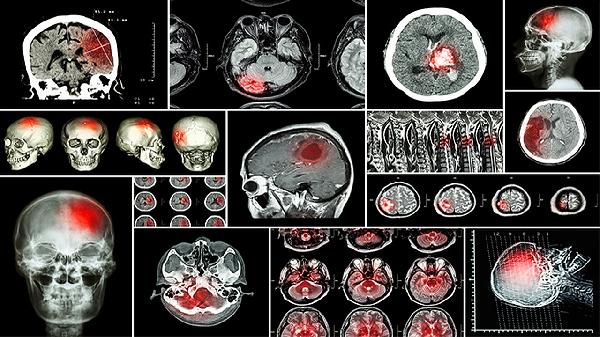

脑水肿和脑积水是两种不同的疾病,它们在成因、表现以及治疗方法上都有明显区别。脑水肿指的是大脑组织内部水分过多,导致脑部体积变大;而脑积水则是由于脑脊液的流动受阻,使得脑室系统膨胀。

脑水肿通常由头部外伤、中风、颅内感染或肿瘤压迫等引起。当脑组织缺血、缺氧或出现炎症时,毛细血管的通透性会增强,导致水分进入细胞间隙。患者可能会有头痛、恶心、意识模糊等症状,严重时甚至可能引发脑疝。治疗时要从病因入手,比如使用甘露醇注射液来降低颅内压力,配合呋塞米片帮助身体排出多余水分,必要时还可考虑进行去骨瓣减压手术。

脑积水多是因为脑脊液分泌过多、吸收不良或者循环路径受阻,常见于先天性结构异常、蛛网膜下腔出血后遗症或脑膜炎等情况。主要症状包括头围增大、走路不稳、记忆力下降,婴儿则可能出现前囟门鼓起。治疗方式主要是恢复脑脊液的正常循环,比如通过脑室腹腔分流术或第三脑室造瘘术,术后可能需要长期服用乙酰唑胺片来控制脑脊液的生成。